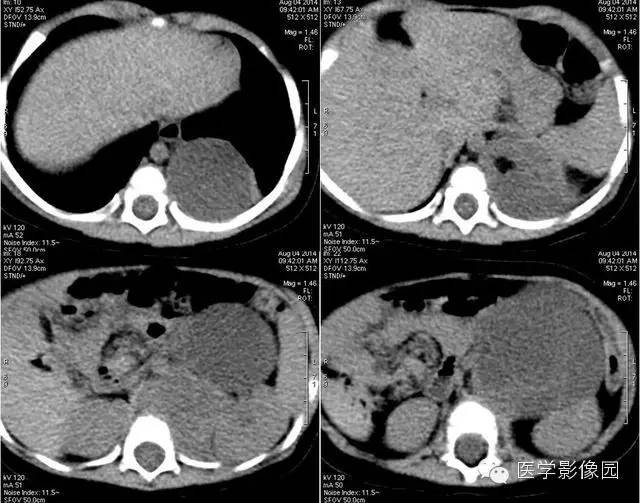

1——平扫

小儿畸胎瘤好发于身体中线及两旁,多发生在骶尾部、腹膜后、纵隔、卵巢等部位,是腹膜后常见的实体瘤之一,发病率仅次于肾母细胞瘤和神经母细胞瘤。

畸胎瘤是由两个或三个原始胚层组织演化而来的胚胎性肿瘤,大体上囊性、实性或囊实性兼有。囊性畸胎瘤又称皮样囊肿,仅含表皮及其附属成分,基本上均为良性。实性畸胎瘤含有三个胚层成分。按组织学分类可分为良性畸胎瘤和恶性畸胎瘤。良性畸胎瘤由分化良好的成熟组织构成,故又称为成熟畸胎瘤,瘤体囊性部分多于实质部分,小儿中绝大部分均为良性畸胎瘤。恶性畸胎瘤由胚胎发生时期的未成熟组织构成,实质部分常多于囊性部分,恶性畸胎瘤在小儿中十分少见。小儿畸胎瘤以女性多见,男女之比约为1:3-4,腹部包块和腹胀为腹膜后畸胎瘤主要的临床表现,患儿一般状况良好。